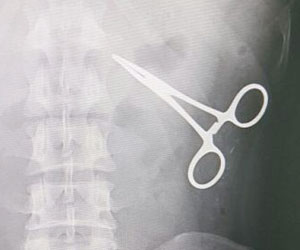

وأوضح المالكي أن "مسؤولي المراقبة بالمركز الصحي أجروا الكشف الظاهري على الحاج، ولما لم تتوافر أي أجهزة معدنية بحوزته، تم تحويله إلى غرفة الأشعة، وكانت المفاجأة التي أظهرتها الصورة الإشعاعية وجود مقص معدني مستقر داخل التجويف البطني له، وبإخبار الحاج أبدى استغرابه، وبسؤاله عن سبب وجوده أبدى عدم معرفته بذلك، وذكر أنه خضع لعملية جراحية في موطنه قبل 15 عاما، وتم إخباره بخطورة الوضع".